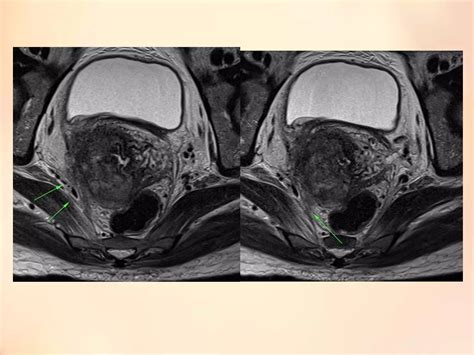

• MRI (Magnetic Resonance Imaging): Highly effective for looking at soft tissues and determining the tumor size and local spread.